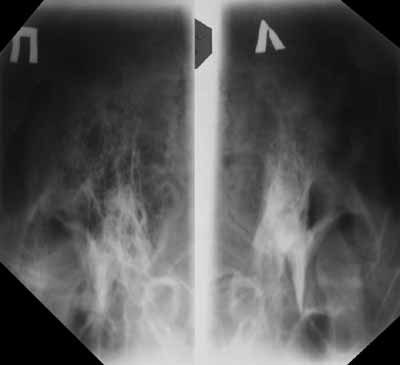

Рис. 3б. Латентный мастоидит. В проекции Майера затемнен вход в антрум слева.